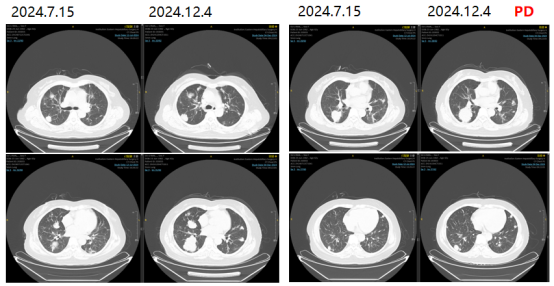

2024-12-04复查胸部CT提示两肺多发转移瘤,较前进展。

图10影像学复查结果